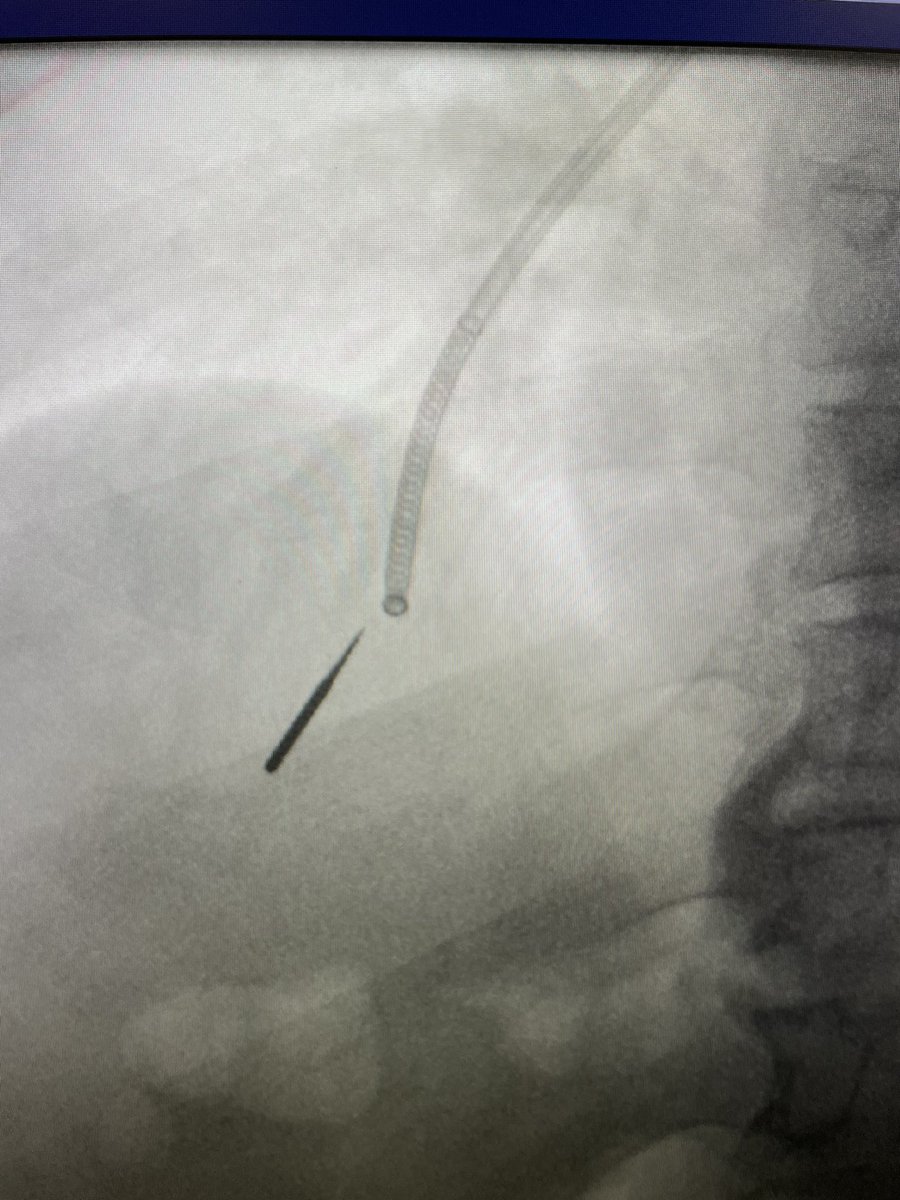

Ramsy Abdelghani, MD

A (useful?) workaround: This patient had radiation to a LUL lesion (First image). Another more apical PET-avid lesion arises, but to get to the apical lesion I had to go through the radiated area. I found the airway was very dense and severely stenosed (Second image).